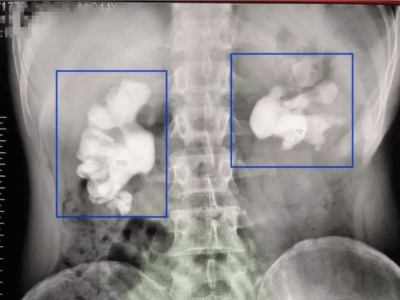

那雙腎結(jié)石引起腎功能損害的情況多不多呢?崔院長(zhǎng)說(shuō)還真不少,在雅安仁康醫(yī)院基本上每月都要遇到?!爸斑€遇到一位住在市區(qū)魏家崗的張大爺,雙腎輸尿管、膀胱都長(zhǎng)了結(jié)石,由于就診太晚腎損害已到尿毒癥階段,靠透析維持了一段時(shí)間生命,現(xiàn)已去世。”

泌尿系結(jié)石包括腎結(jié)石、輸尿管結(jié)石、膀胱結(jié)石和尿道結(jié)石,是常見(jiàn)的臨床疾病之一,每一百個(gè)人中大約有5個(gè)人有泌尿系結(jié)石。四川地區(qū)由于水質(zhì)和生活習(xí)慣等原因患泌尿系結(jié)石的人也特別多。由于很多人對(duì)結(jié)石的不了解,常常導(dǎo)致一個(gè)小小的結(jié)石就引起自身腎臟的損害。很多人以為尿結(jié)石主要的危害就是引起腰痛和血尿,其實(shí)這只是表面現(xiàn)象。

崔院長(zhǎng)介紹,尿結(jié)石比較嚴(yán)重的危害是阻塞尿路引起腎積水,從而導(dǎo)致腎臟功能損害,甚至腎臟完全壞死。如果影響了兩個(gè)腎臟,很可能導(dǎo)致尿毒癥的發(fā)生。